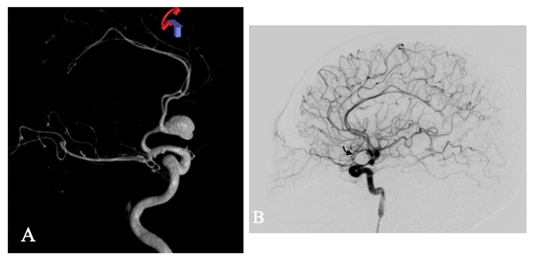

La angiografía de sustracción digital reveló un aneurisma sacular en la arteria comunicante anterior de 16 x 11 mm con cuello de 3 mm (figuras 1A-B), el cual se trató mediante embolización con coils con pequeño remanente de cuello tipo Raymond II.

El día nueve el paciente presentó cefalea intensa y aumento del índice de Lindegaard izquierdo hasta 8,15 (figuras 2A-B). Por lo anterior, se realizó angiografía que mostró vasoespasmo en las arterias cerebrales anteriores y arteria cerebral media izquierda, por lo que se administró terapia de infusión intrarterial de nimodipino con mejoría clínica y angiográfica. En el cuadro 1 se aprecia la correlación entre el déficit neurológico, el índice de Lindegaard elevado (mayor a seis) y la presencia del vasoespasmo documentado angiográficamente.